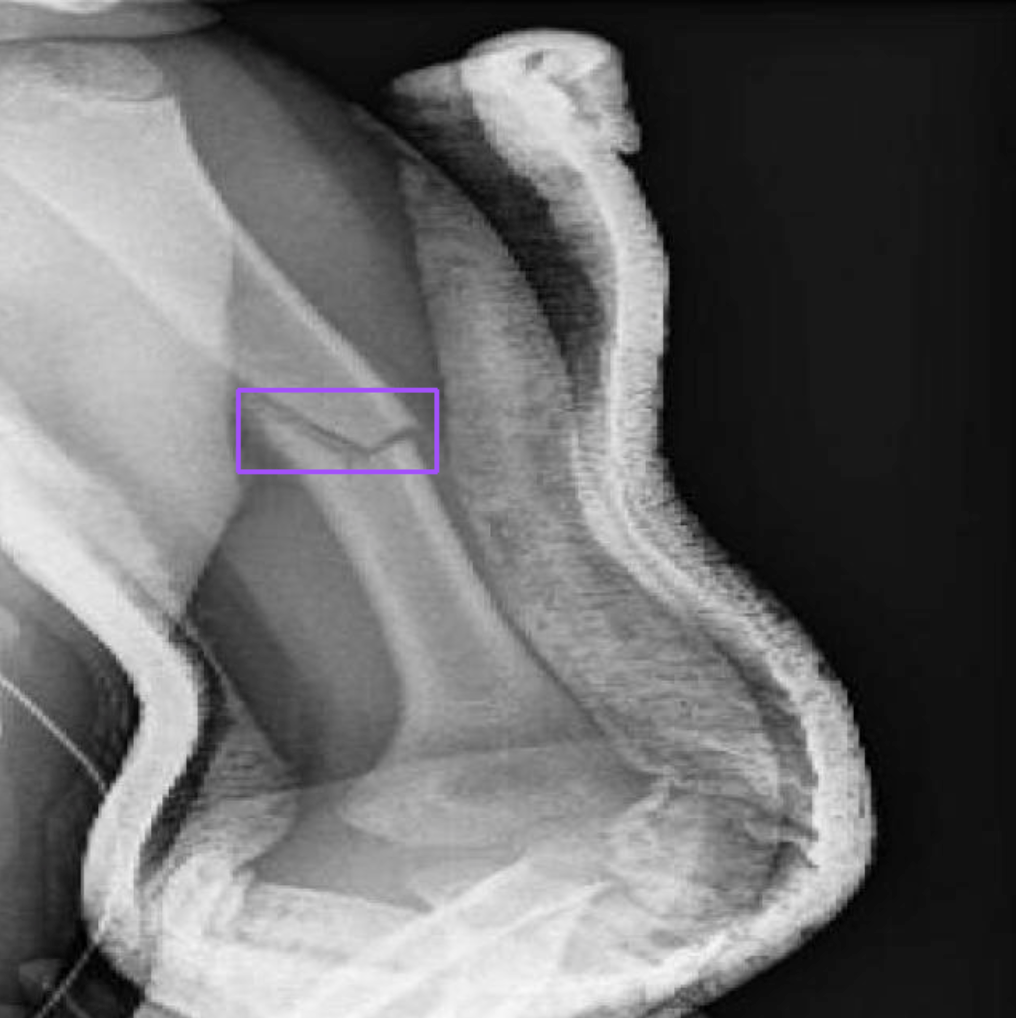

display(HTML(html_out))Here is a selection of results from our model when run on the validation dataset for our project:

In this image, there are images from the validation set, with pink bounding boxes that correspond to detections from the model, and text labels on the right that tell us what class was identified ("fracture").